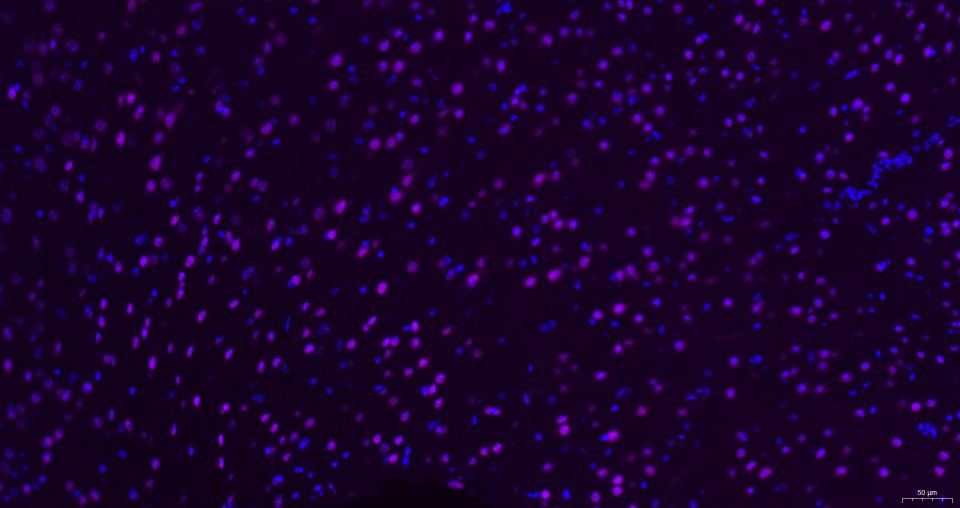

Paraformaldehyde-fixed, paraffin embedded Human Brain; Antigen retrieval by boiling in sodium citrate buffer (pH6.0) for 15 min; Antibody incubation with AKT1 Monoclonal Antibody, Unconjugated(bsm-52010R) at 1:200 overnight at 4°C, followed by a Cy5 conjugated Goat Anti-Rabbit IgG (bs-0295G-Cy5)antibody at 37°C for 90 minutes, DAPI (blue, C02-04002) was used to stain the cell nuclei.